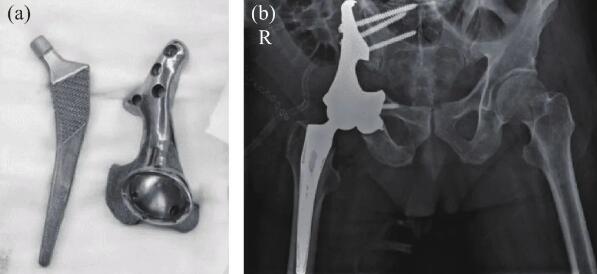

骨盆部位手术一直是骨科手术中的难题之一。2022年,大连大学附属中山医院为骨盆肿瘤导致右髋关节变形的患者进行了3D打印钽半骨盆及髋关节假体植入(图10(a)),进一步拓宽了3D打印多孔钽的应用。该患者受损部位大,需要切除髂骨、髋臼及部分或全部耻骨和坐骨,切除及植入手术难度高。该院通过3D打印为患者定制的植入体与患者切除后缺损部位高度匹配(图10(b)),节省了植入手术时间。

图10 3D打印钽金属骨盆和髋关节:(a)打印成品;(b)植入人体后X光照片